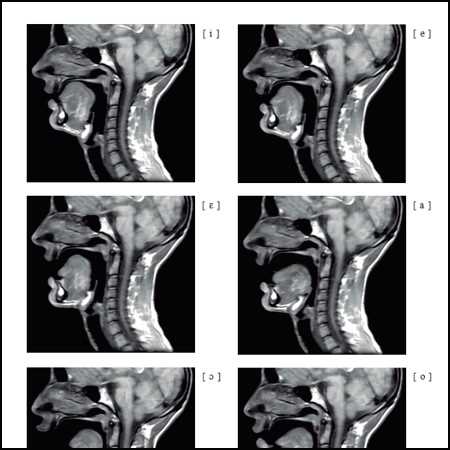

Imatges de Ressonància Magnètica